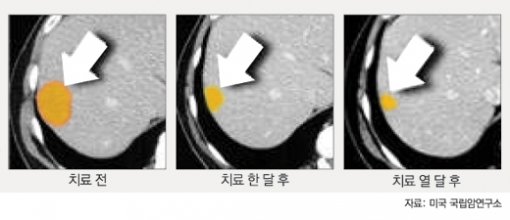

유전자가 바뀐 T세포는 다시 환자들에게 이식됐다. 18개월 정도 치료한 결과 말기 단계였던 52세의 한 남성 환자는 왼팔 피부에서 겨드랑이로 번졌던 종양이 사라졌고, 간에 있던 또 다른 종양은 89%까지 사라져 수술로 제거할 수 있을 정도의 크기가 됐다. 종양이 폐로 퍼진 30세 남성 환자는 현재 완치 상태다.